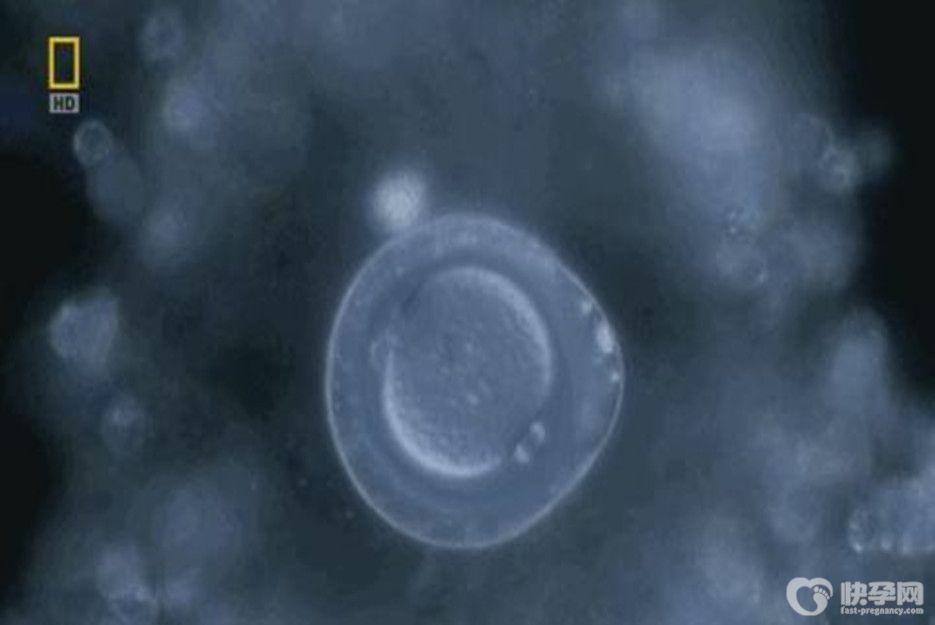

精卵子取出体外之后在体外结合受精,正常的受精卵进一步分裂发育成第一、二、三天的胚胎这个阶段就叫做卵裂期胚胎,俗称就是胚胎。